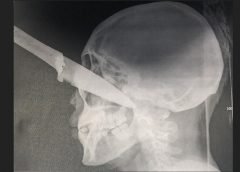

Leer Mas...Salta- Las mujeres que clavaron un cuchillo en el ojo a la joven de El Galpón fueron imputadas- Argentina

El hecho ocurrió frente un consultorio médico particular en calles Juan Carlos Dávalos y avenida Islas Malvinas, donde la víctima se encontró con las acusadas. Según consta en la etapa inicial de la investigación, cruzaron palabras por pleitos pasados y al salir, la joven fue atacada por el grupo de mujeres. Una de ellas le clavó un cuchillo en el...

Leer Mas...Extrema violencia entre mujeres en El Galpón: le incrustó un cuchillo en el ojo

Un hecho de extrema violencia se vivió el miércoles por la tarde en la vía pública de la ciudad El Galpón cuando una mujer le incrustó un cuchillo tipo puñal en uno de sus ojos a una joven de 23 años en medio de una discusión. Florencia Ruíz es el nombre de la víctima que recibió un puntazo en su...